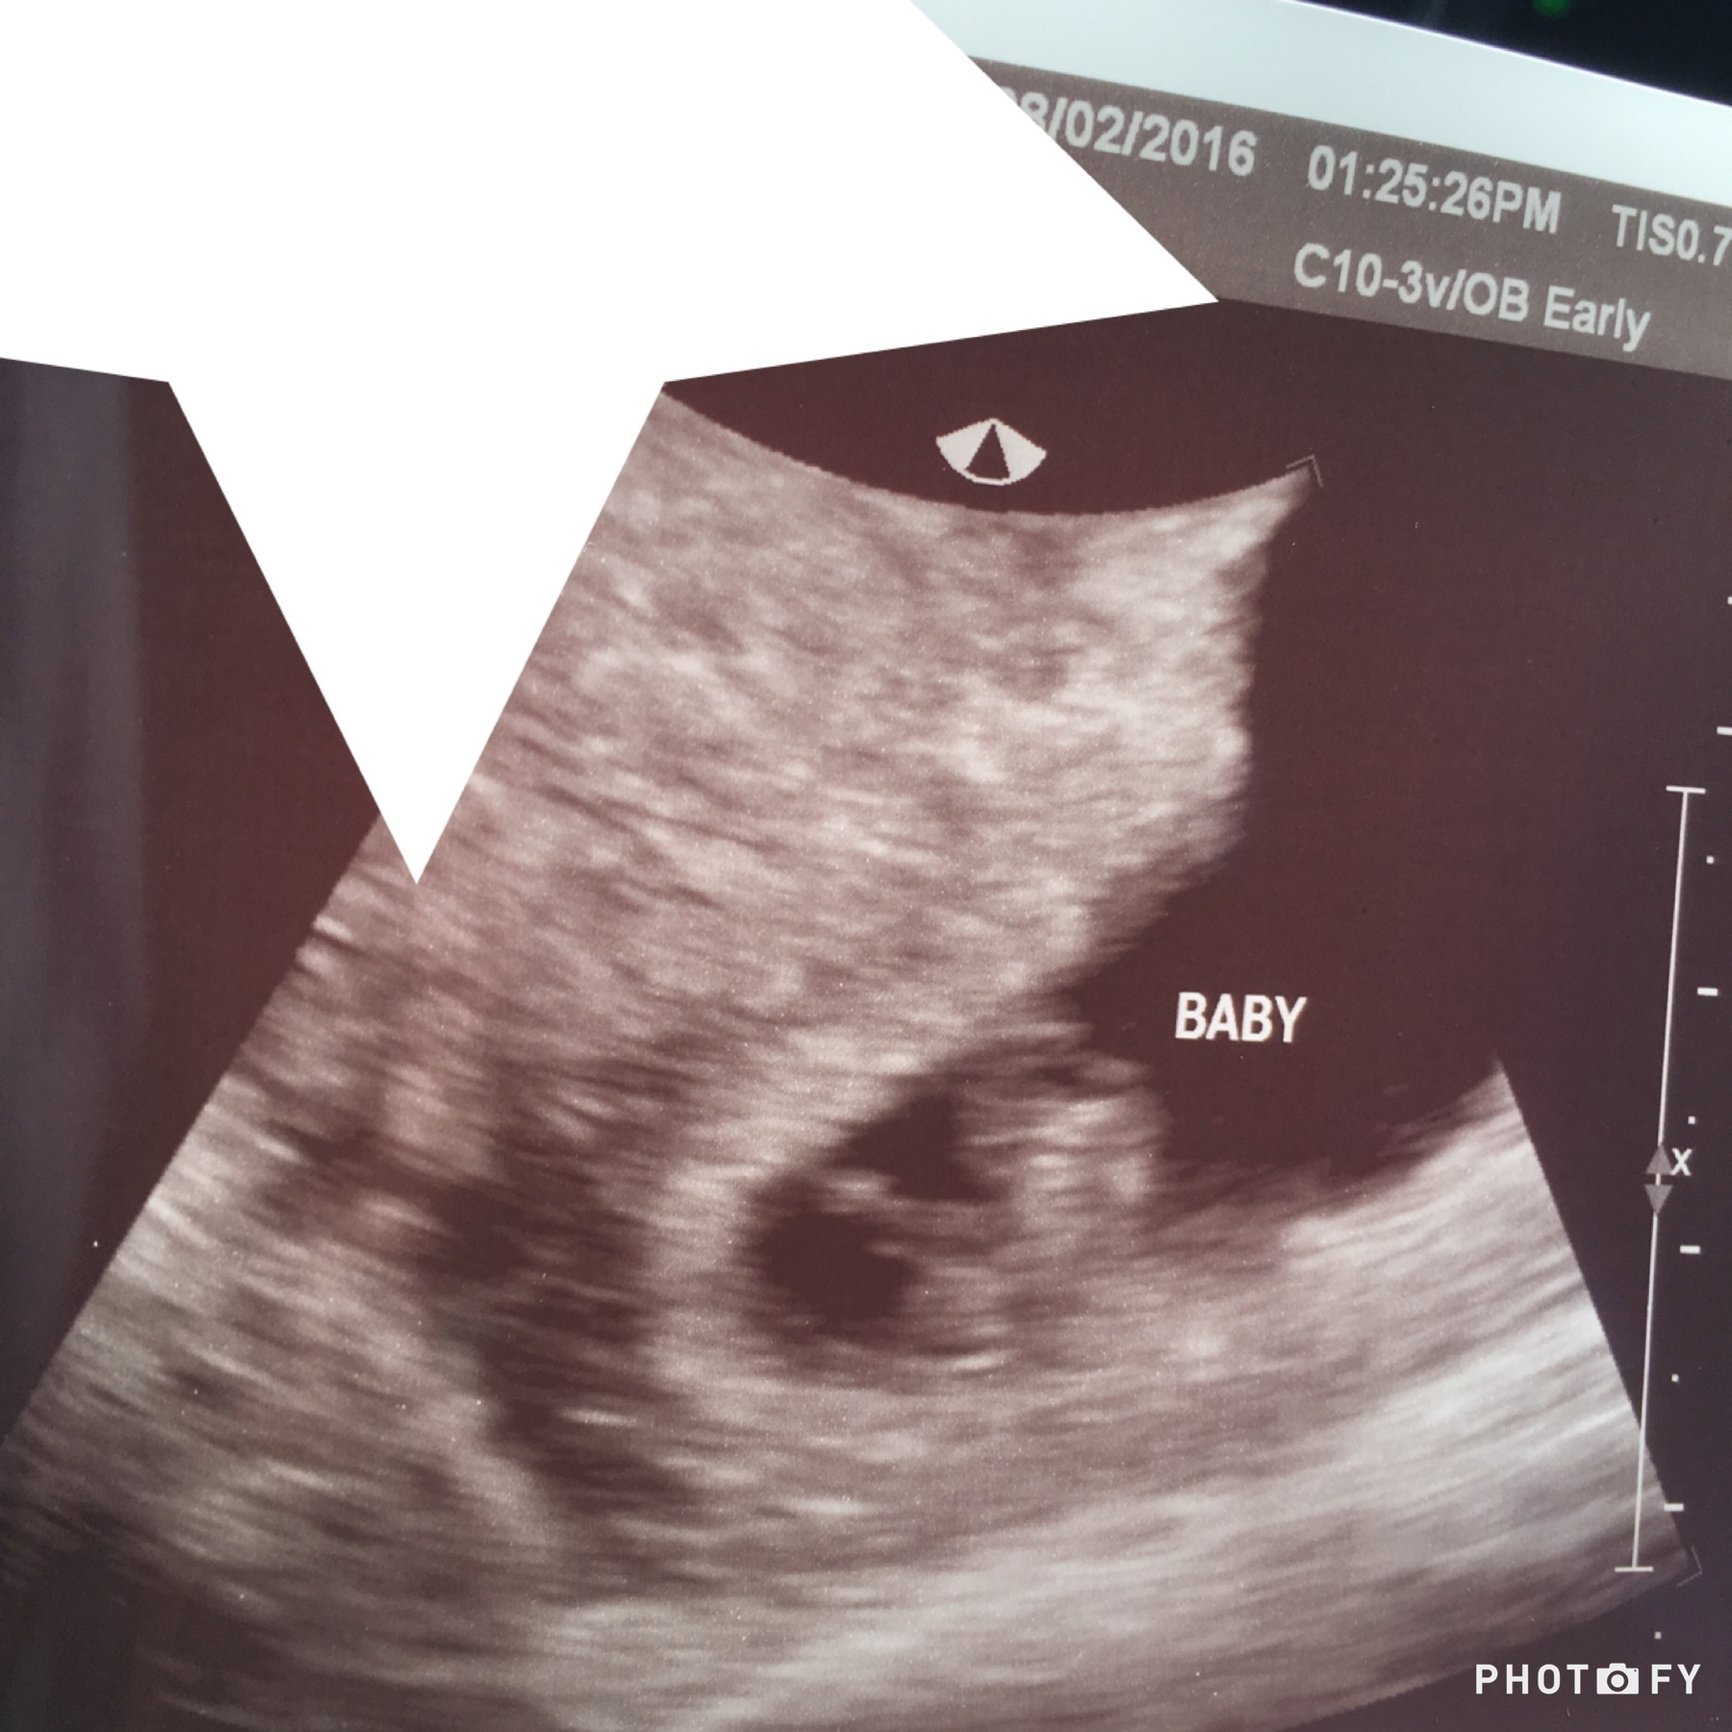

After crazy, intermittent pain the last 72 hours, I ended up with an ultrasound today. Should be about 6 weeks, measuring a little under at 5 weeks 3 days, but she said very typical for measurements to me off this early. We could see the heart beat at 114. It will be more accurate when I go at 8 weeks. Oh and the pain they are pretty sure was a kidney stone... Baby is just fine! It's the little blub under the word!